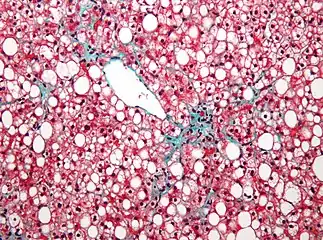

| Micrograph showing a fatty liver (macrovesicular steatosis), as seen in non-alcoholic fatty liver disease. Trichrome stain. | |

Pathology

The fatty change represents the intracytoplasmatic accumulation of triglycerides (neutral fats). At the beginning, the hepatocytes present small fat vacuoles (liposomes) around the nucleus (microvesicular fatty change). In this stage, liver cells are filled with multiple fat droplets that do not displace the centrally located nucleus. In the late stages, the size of the vacuoles increases, pushing the nucleus to the periphery of the cell, giving a characteristic signet ring appearance (macrovesicular fatty change). These vesicles are well-delineated and optically "empty" because fats dissolve during tissue processing. Large vacuoles may coalesce and produce fatty cysts, which are irreversible lesions. Macrovesicular steatosis is the most common form and is typically associated with alcohol, diabetes, obesity, and corticosteroids. Acute fatty liver of pregnancy and Reye's syndrome are examples of severe liver disease caused by microvesicular fatty change.[19] The diagnosis of steatosis is made when fat in the liver exceeds 5–10% by weight.[13][20][21]